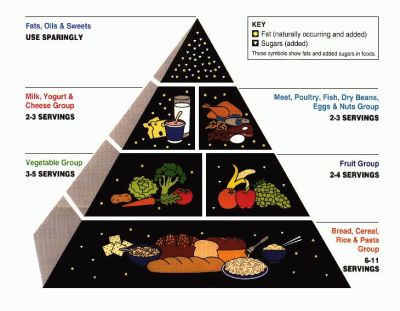

Diet and activity

Photographs: http://www.nal.usda.gov/fnic/Fpyr/pyramid.gif/Wikimedia Commons

People who have a poor diet, do not indulge in enough physical activity, or are overweight may be at an increased risk of several types of cancer -- of the colon, uterus and prostate.

Lack of physical activity and being overweight are also risk factors for cancers of the breast, colon, esophagus, kidney and uterus.